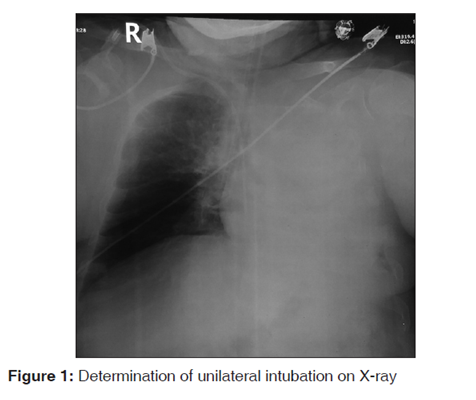

3.诊断由颈部或纵隔肿块引起的气管偏离或压迫,例如甲状腺癌,食道癌和颈淋巴结肿大[图2]。

(甲状腺肿块引起的气管偏移和压迫。注意在PA视图(a)中有明显的偏差,而在侧视图中则有压缩。)